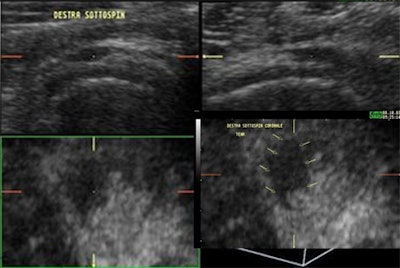

| Multiplanar demonstration of a post-traumatic partial tear on the bursal aspect of the rotator cuff (infraspinatus tendon). The coronal plane and 3D reconstruction demonstrate dramatically the full extent of this tendon tear (indicated by the arrows), which initially on the transverse and longitudinal planes seems less extensive. |

![]() |